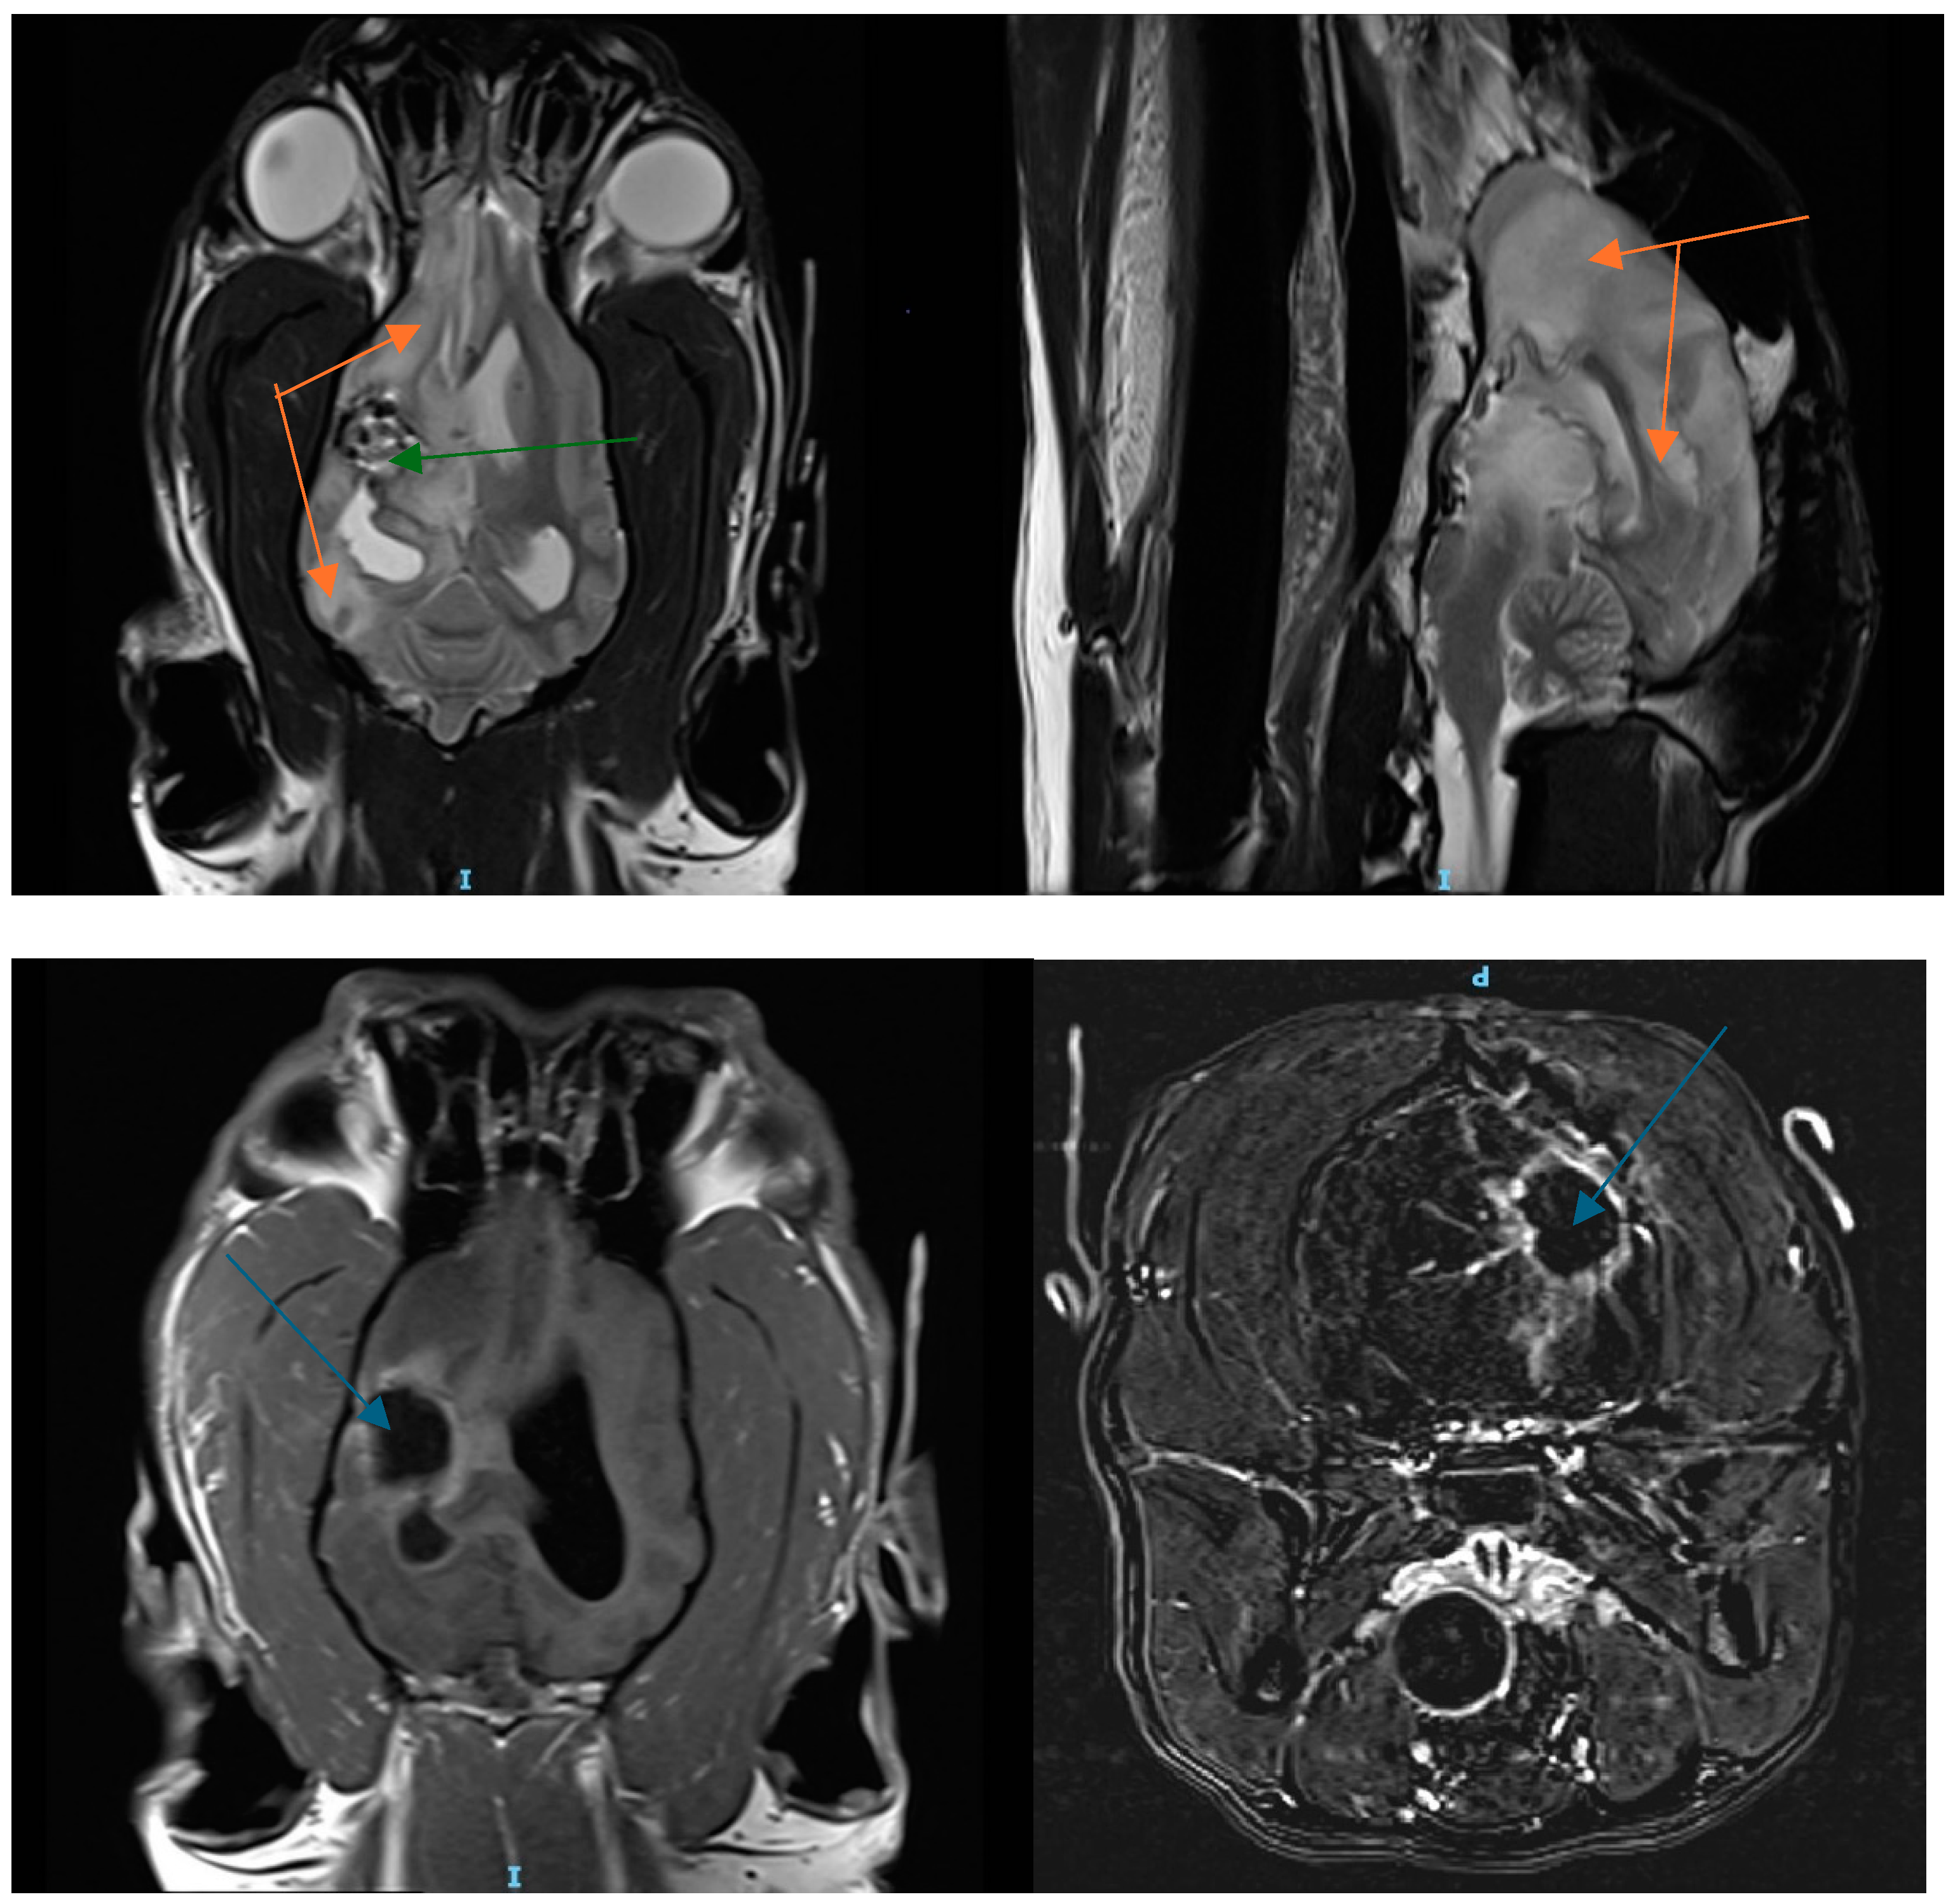

3.1. Patient History